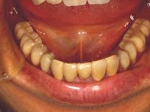

術後(鏡像)

術後口腔内(正面観)もう入れ歯は要らなくなりました。